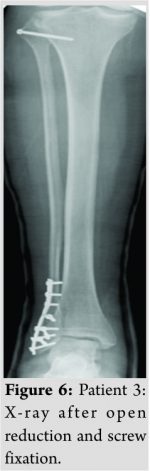

Case 2: A 63-year-old man caught his right foot in a net and fell immediate pain and minimal swelling proximally on the leg. It was diagnosed as a tibiofibular dislocation. A computed tomography (CT) scan was conducted to confirm a dislocation in an anterolateral direction while waiting for surgery, the dislocation spontaneously reduced. The patient was treated with a cast, with non-weight bearing for 2 weeks. Six months after injury, the patient was without symptoms. Case 3: A 45-year-old woman got a large object on the proximal part of her right leg. She had an open wound over her proximal fibula. We found a posteromedial dislocation. Through the wound, the fibular head dislocation was reduced and temporarily (for 6 weeks) fixated with a screw. At 6 months follow-up, there was no restriction of movement in the knee and the proximal tibiofibular joint was stable. She still had occasional pain with full weight bearing.

A 45-year-old woman was walking her dog when she got a large sheet of wood on the proximal part of her right leg. Stability testing of the right knee joint showed no instability and there was no peroneal nerve palsy. She had surgery for a lateral malleolar fracture. Peroperatively, we found an unstable, posteromedial dislocation of the fibular head. Through a deep wound (Fig. 5), the fibular head dislocation was reduced and temporarily (for 6 weeks) fixated with a screw (Fig. 6). Postoperatively, she developed a moderate form of complex regional pain syndrome that led to a slow recovery. She was non weight bearing for 6 weeks because of her malleolar fracture. At 6 months follow-up there was no restriction of movement in the knee and ankle. The proximal tibiofibular joint was stable. She still experienced occasionally some pain with full weight bearing.

A traumatic dislocation of the tibiofibular joint is an uncommon injury, comprising <1% of all knee injuries [4]. Anterolateral dislocations are most common (85%), followed by posteromedial (10%) ,and superior (2%) [5].The literature has mentioned about 140 cases (108 +30) from its first description in 1874 until 2014 [1,4]. They are mostly related to sporting activities [6]. Left untreated, the patient may experience chronic pain and instability in the knee, abnormal gait and reduced sporting performance [7]. Injury to the common peroneal nerve (transient) is rarely (5%) seen especially in posteromedial dislocations [3,8]. A high index of suspicion is required in traumas with lateral knee symptoms and inability to bear weight. The mechanism of the injury and adequate physical examination will lead to right diagnosis. Bilateral AP X-rays (as in our patient 1) may be helpful, but the best option is to perform a CT scan (or magnetic resonance imaging) as we did in our patient 2. The function of the common peroneal nerve should be noted. The best treatment in an acute setting is not known yet. There is some agreement that the initial management of an acute traumatic anterolateral dislocation should be closed reduction (direct posterior pressure to the dislocated fibular head with the knee in (full) flexion and the foot externally rotated, in dorsiflexion and everted) [9]. Others recommend immediate mobilization with the intention to provoke spontaneous reduction [10]. We used spinal anesthesia in our patient 1, but one could try to reduce the dislocation first under local anesthesia in combination with muscle relaxation. This failed in our patient 2. There is no consensus as to the method or duration of immobilization or the weight-bearing status following closed reduction [4,9]. There is at present no clear evidence for restriction of weight bearing or immobilization after a successful closed or spontaneous reduction [4]. We did not use anyspecific post reduction rehabilitation protocol. Open reduction (with primary repair of the ligament structures) and (temporary) fixation are required if the closed reduction fails [9]. In an acute setting of joint instability after closed reduction, the most common surgery described is also open reduction combined with (temporary) fixation [11]. There is also no consensus as to the method and the duration of the temporary fixation. This varies between Kirschnerwire(s), pin(s), or screw(s) for 3–26 weeks in the literature [4,11]. In our patient 3, we chose one-screw fixation for 6 weeks, with full range of motion in the knee and full restriction of weight bearing as long as the screw was in place, which we thought was a reasonable protocol based on the existing literature. We have no reason to believe that the residual symptoms in patient 3 were caused by our setup. We have a recorded 6 months follow-up of all three patients. After several years, none of these patients contacted our department/hospital, the only in the region treating these conditions. We have therefore reason to believe that there is no changing or worsening of the patients’ complaints after this first 6 months follow-up.